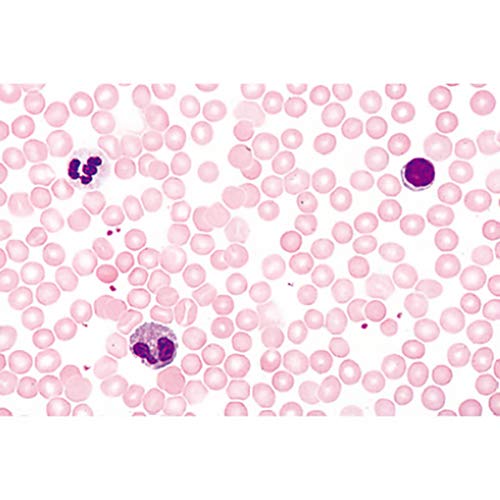

Microscope Slides: 1(d). Trachea, cat, t.s. 2(e). Lung, human t.s. 3(c). Blood, human, Wright stained smear 4(c). Artery, human, t.s., elastica stained